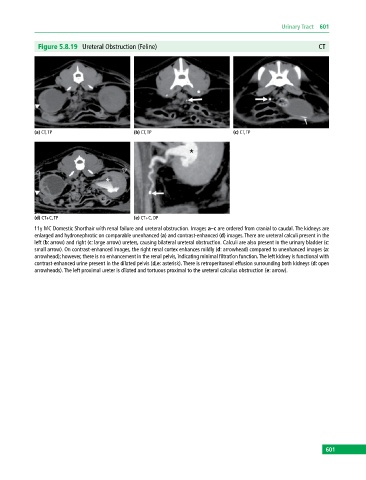

Figure 5.8.19 Ureteral Obstruction (Feline) CT

11y MC Domestic Shorthair with renal failure and ureteral obstruction. Images a–c are ordered from cranial to caudal. The kidneys are

enlarged and hydronephrotic on comparable unenhanced (a) and contrast‐enhanced (d) images. There are ureteral calculi present in the

left (b: arrow) and right (c: large arrow) ureters, causing bilateral ureteral obstruction. Calculi are also present in the urinary bladder (c:

small arrow). On contrast‐enhanced images, the right renal cortex enhances mildly (d: arrowhead) compared to unenhanced images (a:

arrowhead); however, there is no enhancement in the renal pelvis, indicating minimal filtration function. The left kidney is functional with

contrast‐enhanced urine present in the dilated pelvis (d,e: asterisk). There is retroperitoneal effusion surrounding both kidneys (d: open

arrowheads). The left proximal ureter is dilated and tortuous proximal to the ureteral calculus obstruction (e: arrow).